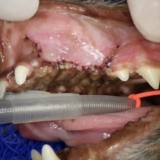

胃を切開し、異物を取り出しました。やはり大きな「石」でした。

慎重に石を取り出しているところ

角があり尖っていた。